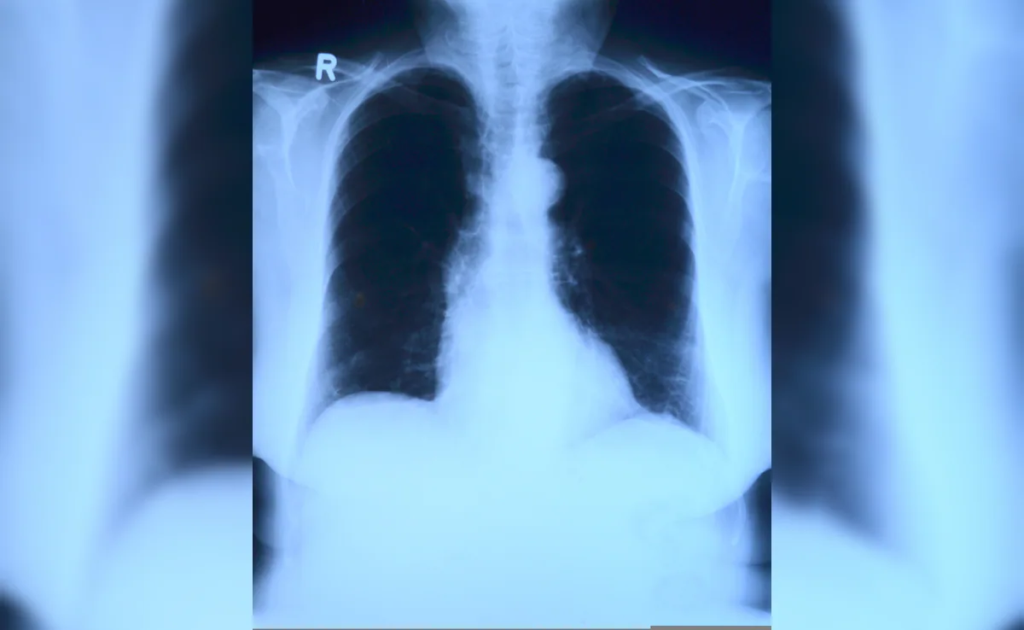

Does AI guess X-ray Results Instead of Reading Them? A Closer Look At The “Mirage Effect”

A new study from Stanford University is stirring an uncomfortable question in the world of medical AI: when an algorithm interprets an X-ray, is it truly “seeing” the image, or just sounding convincing?

The research, co-authored by Fei-Fei Li and titled Mirage: The Illusion of Visual Understanding, suggests that in some cases, AI systems may generate detailed medical interpretations without actually analyzing any image at all.

The “mirage effect” describes a situation where AI models produce confident, structured responses about images they were never shown.

In controlled tests, researchers removed images entirely from datasets but left the accompanying questions unchanged. The results were striking:

• AI systems still generated detailed diagnoses

• They offered step-by-step reasoning

• Accuracy remained surprisingly high, around 70–80%

In other words, the models behaved as if the image were present, even when it wasn’t.

The result is an illusion of perception. The AI appears to interpret an X-ray, but it may actually be predicting what such an interpretation should look like.